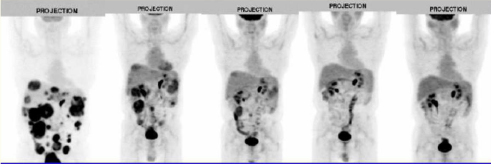

64Cu±ê¼ÇPD-1°ÐµãЧӦͼ

¡÷×ó£ºÒ©ÎïÔÚСÊó¸¹Ç»µÄ¶¯Ì¬ÂþÑÜ£»£»£»£»ÓÒ£ºÒ©ÎïÔÚÄÔµÄÇøÓòÂþÑÜ